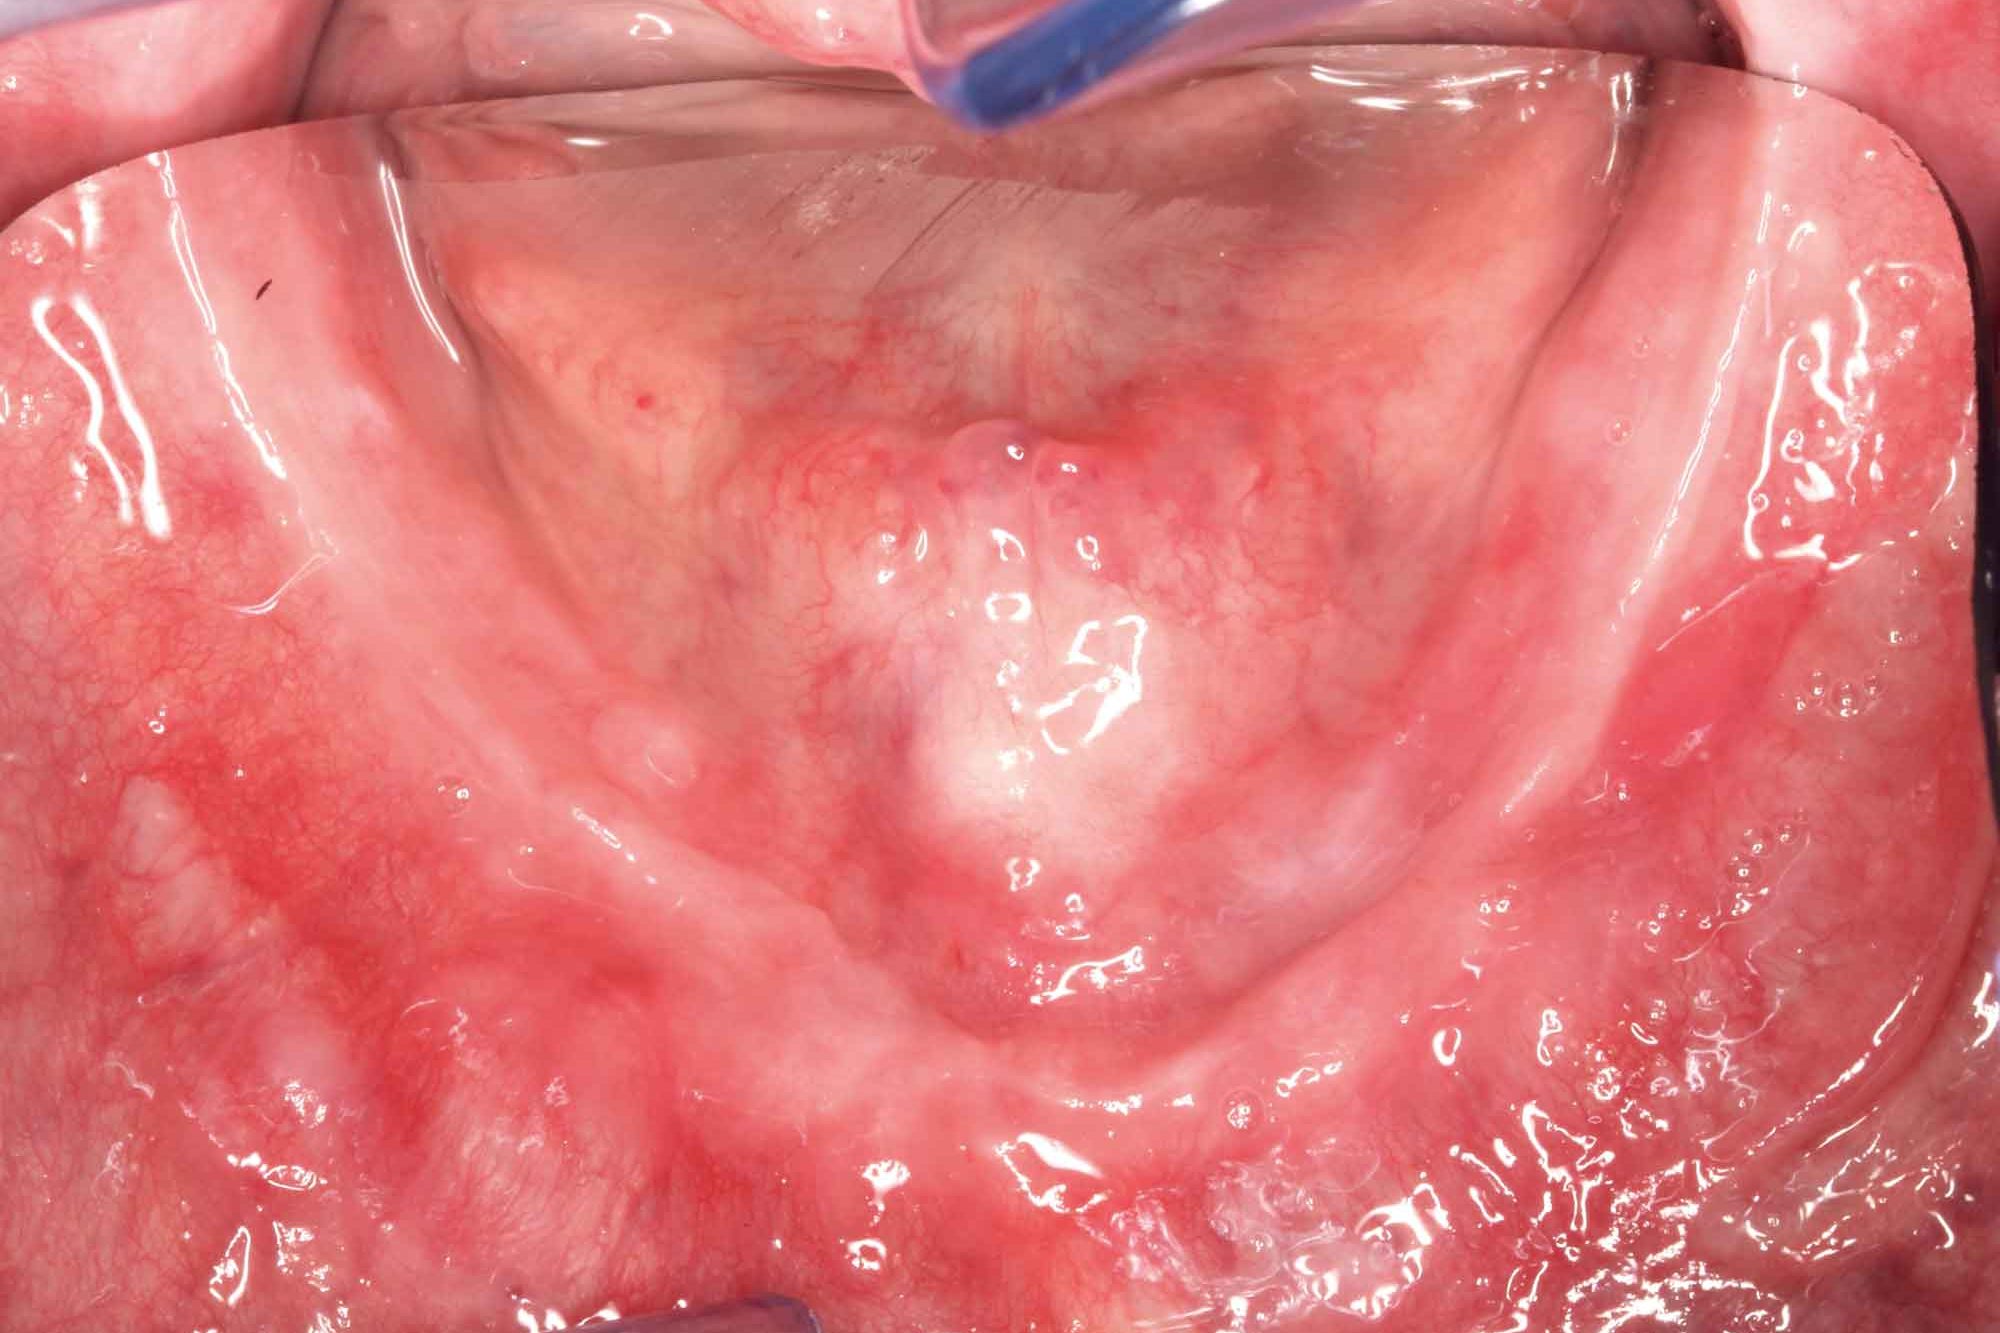

The clinical procedure is described on the basis of a clinical case with very difficult maxillary conditions (Figures 1 and 2). The Wieland digital denture follows the conventional execution for total dentures with some modifications to save time.

• Figures 1 and 2: Both in the upper and lower the patient presents a severe atrophy of the alveolar ridges; it is a case difficult prosthetic solve